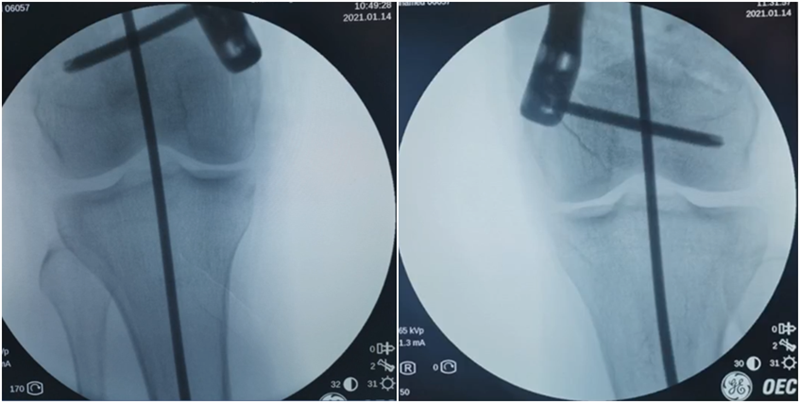

进行翻修,术前力线显示内翻。

术中发现螺钉松动,截骨端出现坎插迹象。

近端螺钉松开,调整力线,重新固定后,在外侧加小钢板抗旋。